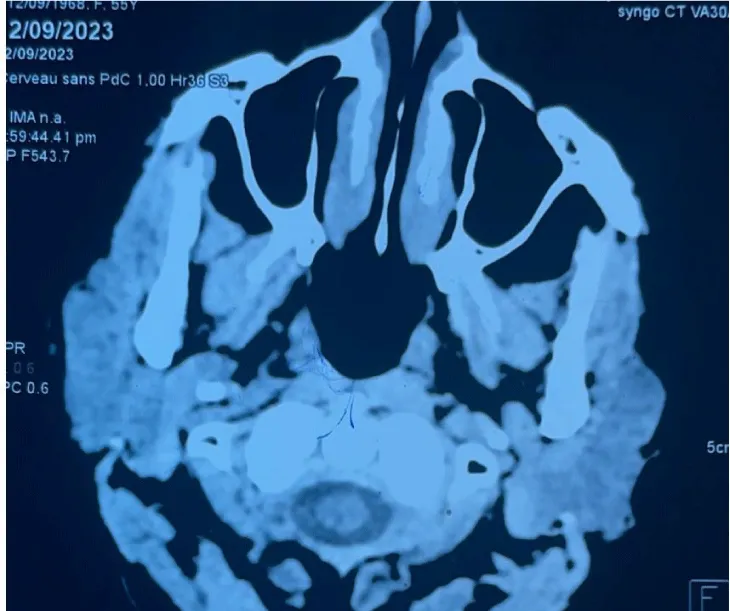

The CT scan revealed the filling of the entire cavum by a tissue process (Figure 1), as well as bilateral axillary and supra-clavicular adenopathies.

Control CT was normal 6 months after chemotherapy (Figure 2). A follow-up panendoscopy revealed a budding mass in the right Rosenmüller fossa and the roof of the cavum. Pathological examination revealed the absence of lymphomatous proliferation.